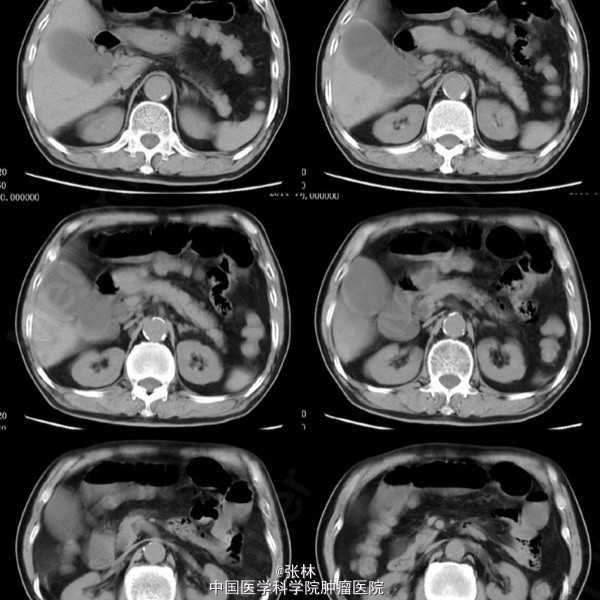

男性,72岁。 主诉:突发腹痛、腹胀伴呕吐1天。 现病史:患者1天前无诱因感全腹部疼痛,呈阵发性绞痛,无放射痛,疼痛开始不剧,伴有畏寒,呕吐胃内容物1次,量约30ml。遂到我院门诊就诊,考虑为急性胃肠炎,予抗炎、解痉护胃等支持治疗,症状未见好转,并进行性加重而入住我科。 专科检查:全腹稍胀,未见肠型及蠕动波,无上腹搏动。腹软,中下轻压痛,无反跳痛。全腹未及肿块,肠鸣音活跃,7次/分。 术中所见:探查见异物位于回肠距回盲部约50cm,大小约8*3*2cm,堵塞肠管,近端肠管充血水肿明显,肠管扩张最大处直径约8cm,未见浆膜层破裂损伤等,系膜无扭转,有少许渗液,探查全部小肠未及肿物腹腔内可见中等量黄色积液,稍浑浊,网膜及腹膜有少量脓苔。洗净腹腔内积液,于肿物边缘对肠系膜缘纵行切开约2cm,取出异物,为半个大小约8*3*2cm的冬菇。